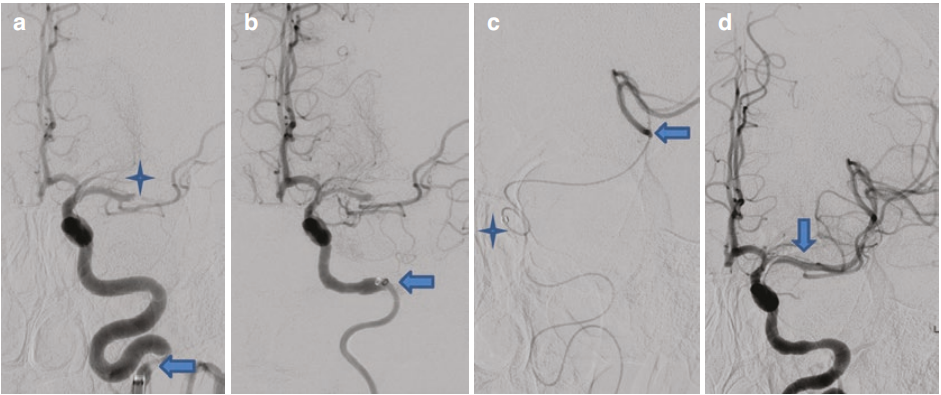

一位32岁男性,既往体健。晨起后出现失语、左向凝视偏斜以及右侧肢体无力症状。该患者接受了静脉溶栓治疗,进一步的神经影像学检查结果支持进行机械取栓(MT)。在清醒镇静状态下为患者实施脑血管造影,结果显示左侧颈内动脉(ICA)终末段完全闭塞。随后,将一根90厘米长的Neuron MAX长鞘置入左侧颈段颈内动脉。在路图引导下,借助Velocity微导管和Synchro 14微导丝,将JET 7抽吸导管向前推进。采用JET 7直接抽吸技术进行了两次操作,使得左侧颈内动脉终末段及大脑中动脉(MCA)M1段实现再通。然而,左侧大脑中动脉M2下分支仍存在持续性远端闭塞。之后,将Velocity微导管穿过左侧M2分支的闭塞部位,超选择性血管造影显示导管尖端位于血栓远端。随后,使用一枚6毫米×40毫米的Solitaire支架取栓器成功进行了第三次取栓操作。最终的数字减影血管造影(DSA)结果显示,左侧大脑中动脉完全再通,达到脑梗死溶栓分级(TICI)3级再灌注水平(见图3) 。

图3颈动脉末端机械取栓术。(a) 在左侧后交通动脉节段水平可见颈内动脉末端完全闭塞(箭头所示)。(b) 运用 JET 7 抽吸导管实现左侧颈内动脉末端及大脑中动脉近端再通(星号所示)。注意大脑中动脉M2下分支远端仍存在残余闭塞(箭头所示)。(c) 将 Velocity 微导管(箭头所示)推进至左侧大脑中动脉M2闭塞段,超选择性血管造影确认其位于血栓远端。随后采用Solitaire支架取栓进行机械取栓操作。(d) 最终数字减影血管造影检查显示,左侧颈内动脉末端及大脑中动脉闭塞处均实现完全再通(箭头所示) 。